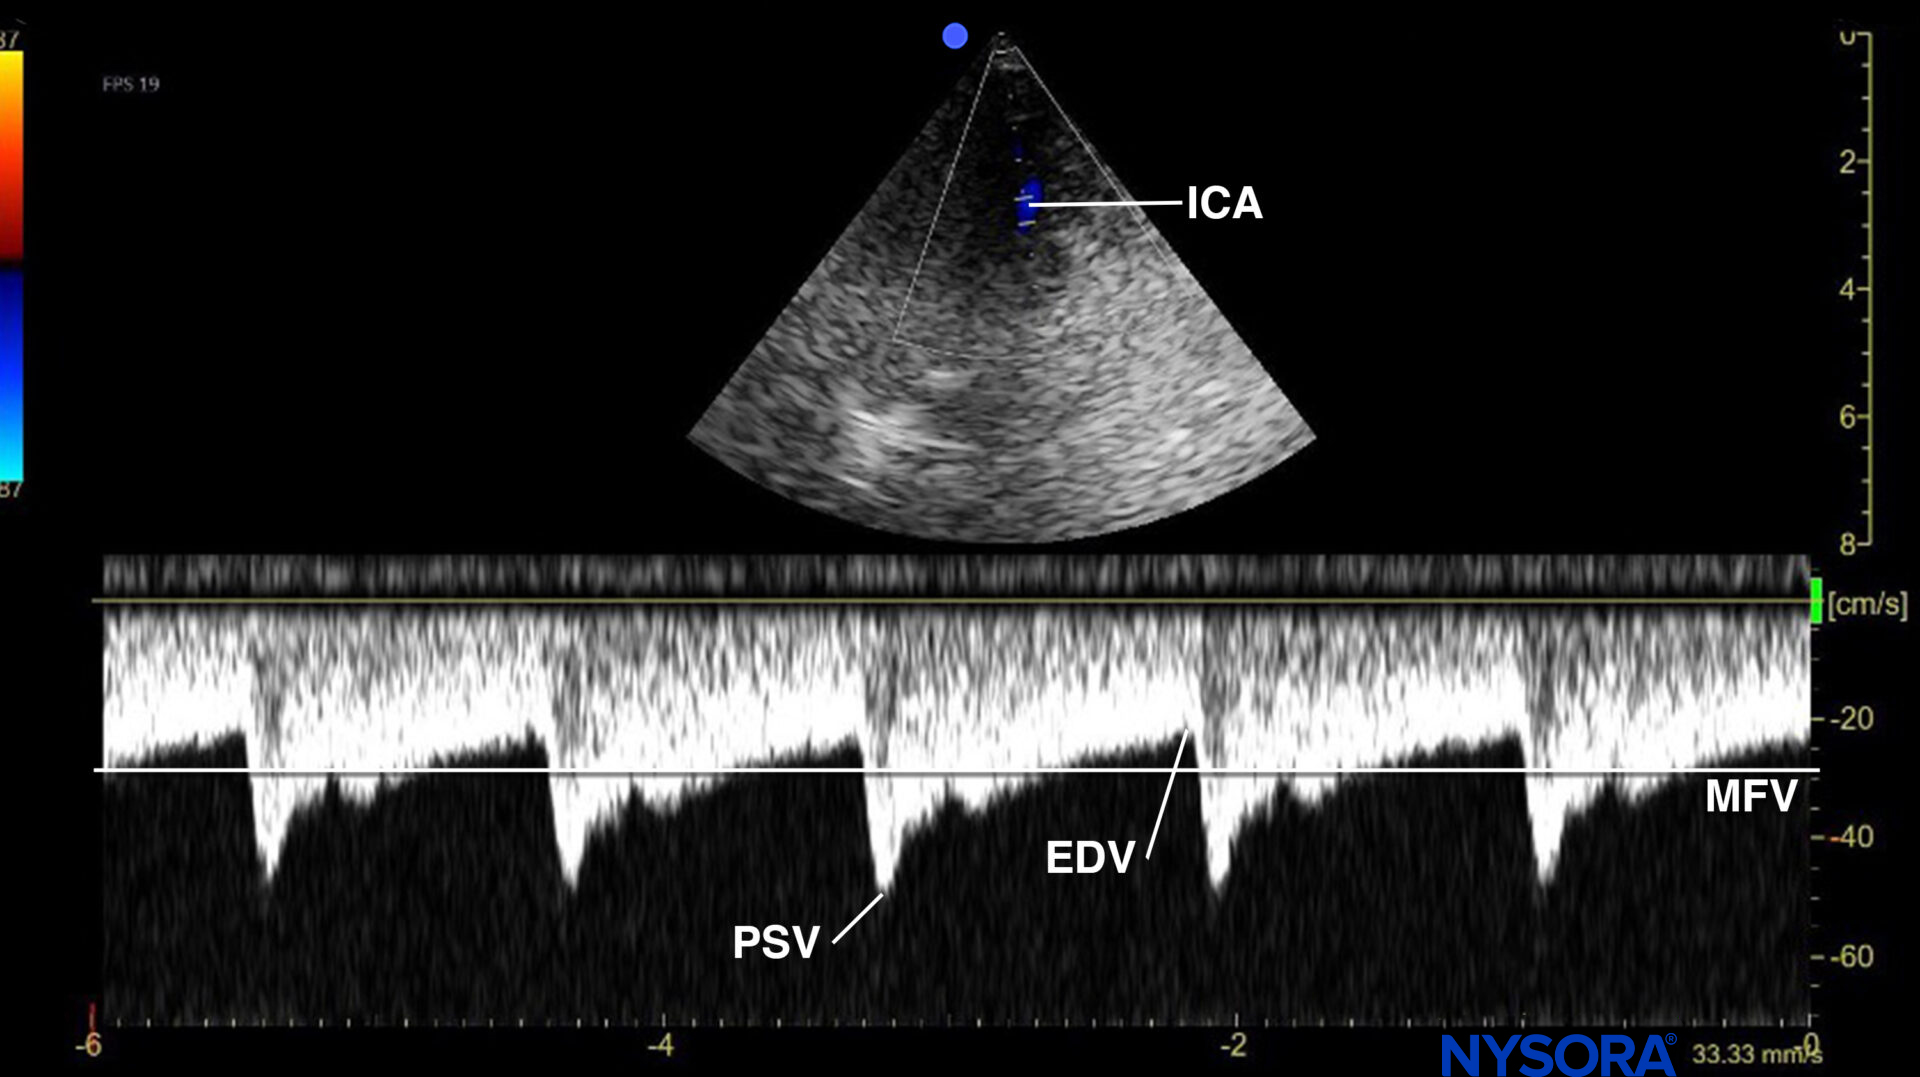

- Measure the flow velocities in the internal carotid artery (ICA).

Use the phased array transducer and position it high in the neck, pointing toward the vertex. Position the Doppler gate on the ICA to obtain the flow velocity, and trace it (usually 4-5 cm).

Pulsed wave Doppler of the flow in the (terminal extracranial) internal carotid artery (ICA). PSV, peak systolic velocity; EDV, end-diastolic velocity; MFV, mean flow velocity.

Low diastolic flow velocities will be present for the external carotid artery. This requires you to redirect the transducer by tilting the transducer more medially. The spectral Doppler waveform of the ICA has the profile of a ‘low resistance’ circulation (gradual decline from PSV to EDV; prominent diastolic flow).